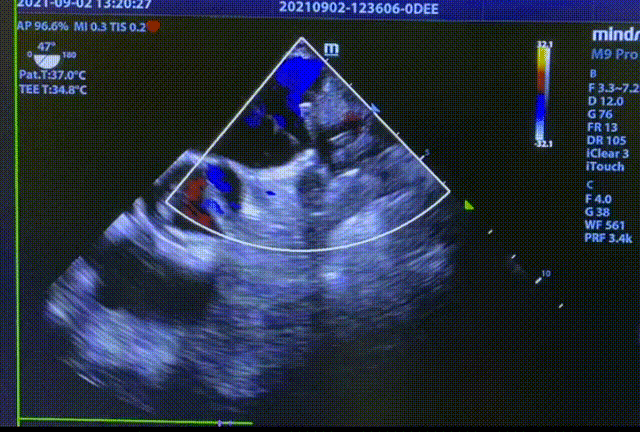

常规肝位造影显示,左心耳锚定区约26mm, 开口约29mm, 因此选择型号为LT-LAA-2834的LAmbre™左心耳封堵器对患者实施封堵。LAmbre™植入过程一步到位,U型钩均完全展开。随后复查造影及TEE结果,封堵盘呈“碗状”形态完美贴合于左心耳口部,无残余分流,牵拉测试稳定,综合评估符合COST原则,随后完美释放,封堵效果理想。术后,患者各项指标正常,身体恢复良好。

封堵器释放后头位与肝位造影

释放后TEE检查(135°)